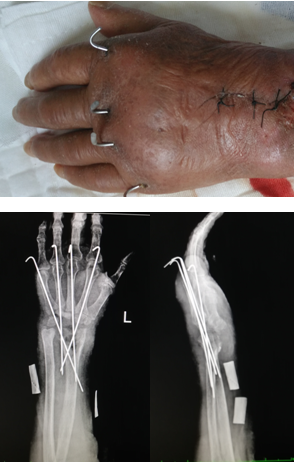

手术案例 —左腕关节结核